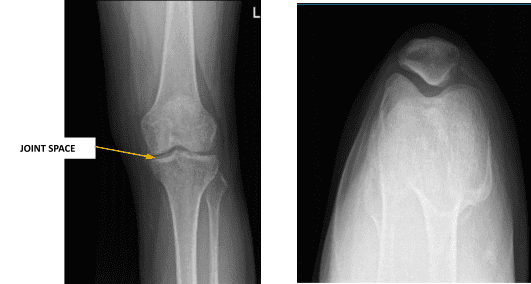

La XR mostró una artrosis muy leve de la rodilla izquierda, preferentemente afectando al compartimento medial. La artrosis se produce debido al desgaste del cartílago en las articulaciones. Normalmente ocurre debido al envejecimiento o al uso intenso de las articulaciones durante deportes, ejercicio u otras actividades.

El espacio articular se estrecha mínimamente en la parte medial del compartimento femorotibial medial. Hay osteófitos marginales muy pequeños. Hay un derrame muy pequeño en la articulación de la rodilla izquierda.

Radiografía de rodilla izquierda con rótula